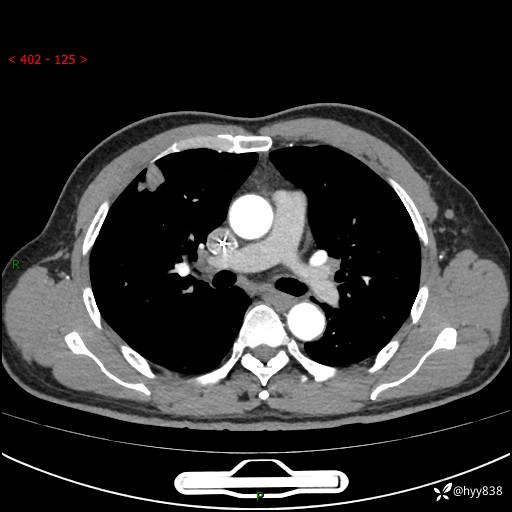

现病史:者10余天前因胸闷就诊于我院心血管内科,行胸部CT提示右肺上叶结节(24mm×16mm),考虑肿瘤性病变可能。无畏寒、发热、盗汗,无咳嗽咳痰,无咯血,无胸痛,无呼吸困难等不适,未予特殊处理。今为求进一步诊治,前来我院就诊,门诊以“肺结节待查”收住入院。 患者自起病来精神、食欲、睡眠尚可,体力下降,体重无明显变化。

胸部CT平扫+增强